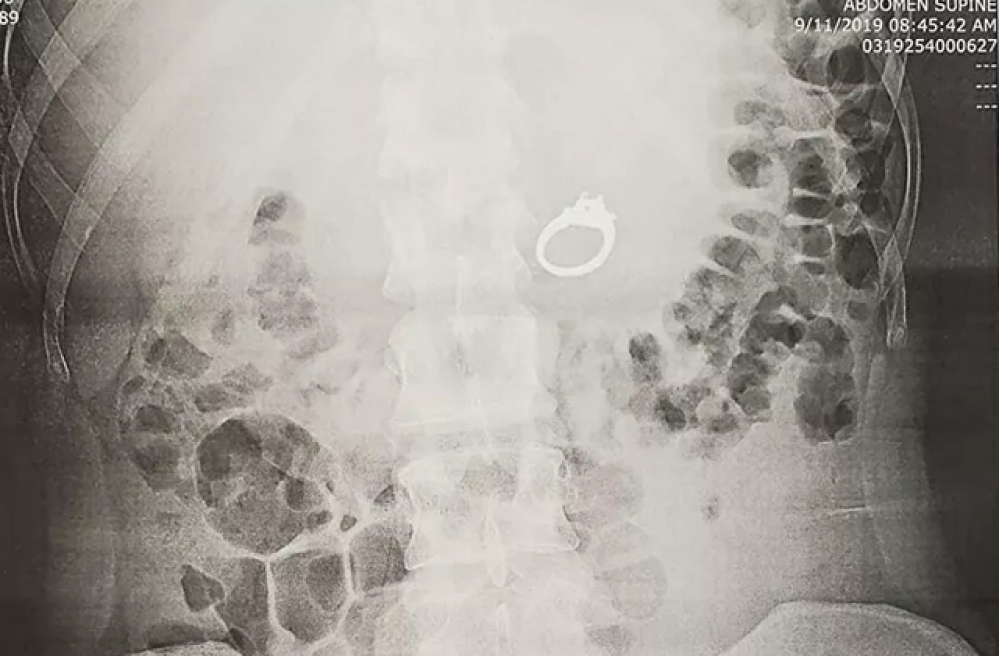

Amerikalı Cenna Evans 2019-cu ildə  “Facebook”da başına gələn bir hadisəni yazmışdı. Ona yuxusunda nişanlısı nişan üzüyünü pis insanlardan qorumaq üçün udaraq gizlətməsini təklif edir. Cenna elə də edir, oyananda isə məlum olur ki, üzük barmağında yoxdur, yuxudakı əmri Cenna həqiqətən yerinə yetirib və üzüyü udub.

Amerikalı xanım baş verənlərə gülərək xilasetmə xidmətinə müraciət edir.  Rentgen şüaları üzüyün həqiqətən mədədə olduğunu göstərir. Qastroenteroloq öz-özünə çıxmasını gözləməməyi məsləhət görərək, onu çıxarmağa qərar verir və nişan üzüyü tibbi yolla qızın mədəsindən çıxarılır.